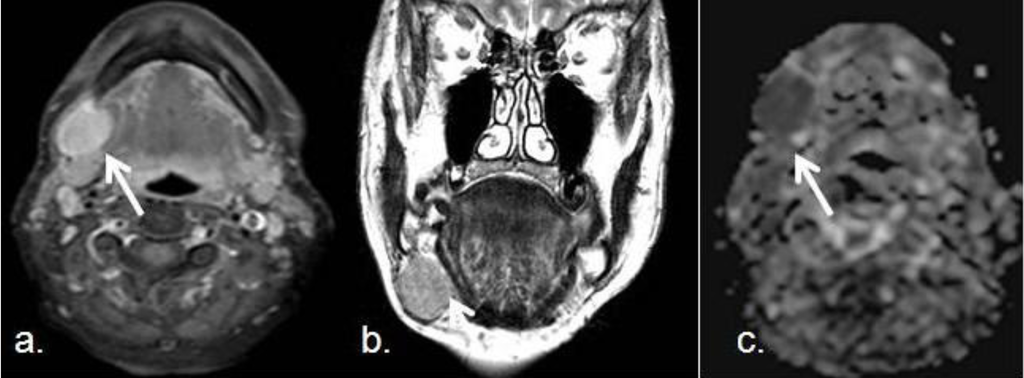

3.2. Salivary Gland Tumors, Orbitary and Pediatric Lesions

- Eida, S.; Sumi, M.; Sakihama, N.; Takahashi, H.; Nakamura, T. Apparent Diffusion Coefficient Mapping of Salivary Gland Tumors: Prediction of the Benignancy and Malignancy. AJNR Am. J. Neuroradiol. 2007, 28, 116–121. [Google Scholar]

- Razek, A.; Gaballa, G.; Elhawarey, G.; Megahed, A.S.; Hafez, M.; Nada, N. Characterization of pediatric head and neck masses with diffusion-weitghed MR imaging. Eur. Radiol. 2009, 19, 201–208. [Google Scholar] [CrossRef]